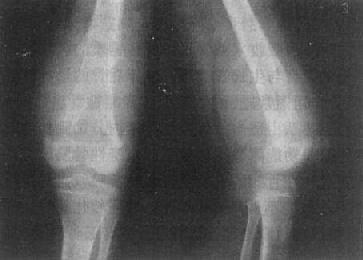

(三)关节退行性变 关节退行性变(degeneration lf joint)早期改变开始于软骨,为缓慢发生软骨变性、坏死和溶解,骨板被吸收并逐渐为纤维组织或纤维软骨所代替,广泛软骨坏死可引起关节间隙狭窄。继而造成骨性关节面骨质增生硬化,并于骨缘形成骨赘。关节囊肥厚、韧带骨化。

关节退行性变的早期X线表现主要是骨性关节面模糊、中断、消失。中晚期表现为关节间隙狭窄、软骨下骨质囊变和骨性关节面边缘骨赘形成,不发生明显骨质破坏,一般无骨质疏松。

这种变化多见于老年,以承受体重的脊柱和髋、膝关节为明显(图2-1-15、16),是组织衰退的表现。此外,也常见于运动员和搬运工人,由于慢性创伤和长期承重所致。不少职业病和地方病可引起继发性关节退行性变。

图2-1-16 关节退行性变-膝关节退行性骨关节病

膝关节的关节间隙变窄,边角锐利,有骨赘形成,关节面平而致密